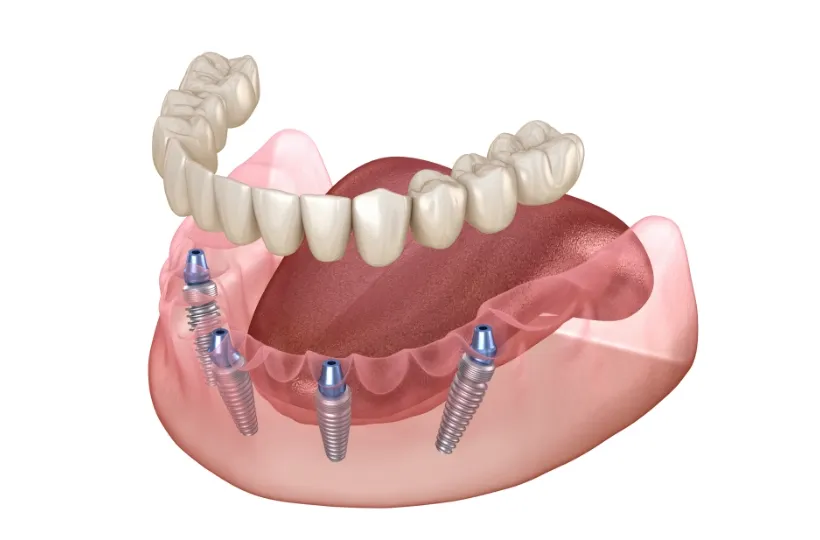

オールオン4・6

歯をすべて失っている方にインプラントを4~6本埋入して、連結した人工歯を支える治療法です。手術回数と埋入数が少ないので、患者さまの体への負担と費用を軽減できます。

オールオン4・6 -